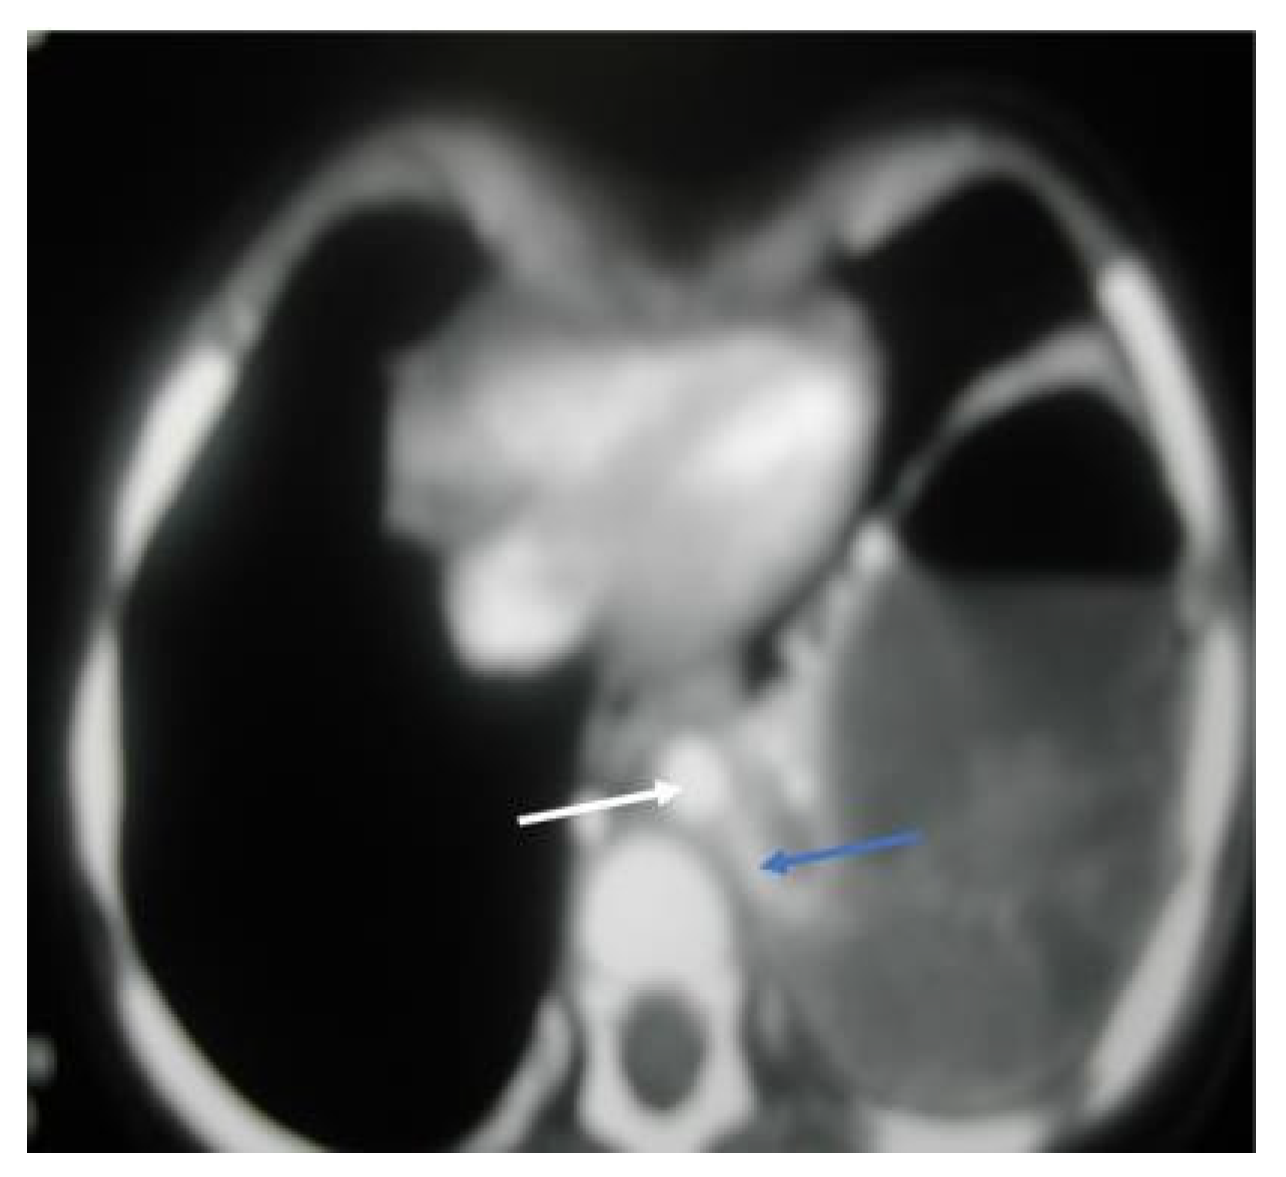

Figure 4. CT chest, axial window, mediastinal view: large, thick wall cavity filled with air fluid with heterogenous opacity. The white arrow shows a descending aorta, while the blue arrow confirms a large feeding vessel to the left lower lobe, a rising and descending aorta, mild compression of left upper lobe, and a mild pectus excavatum.

A 13-month-old girl with complicated pneumonia was referred from a secondary hospital for further evaluation. She was a previously well child with an unremarkable history. She had a flu-like illness and then spiked a high-grade temperature associated with a wet cough and respiratory distress for 3 days. The patient’s condition was diagnosed initially as pneumonia and treated with augmenting for 3 days. Due to inadequate improvement, she was referred to a tertiary center for further management. On physical examination, the patient was ill, with the following vital signs: temperature, 38.7 °C; HR, 130/m; respiratory rate, 60/m; saturation, 88% in room air with a decreased breath sound on the left side. Investigations showed WBC:7.3 k/µL, band: 1.3 k/µL, Hb: 10.4 g/dl, and platelets: 519 k/µL. The chest X-ray suggested complicated pneumonia with a potential lung abscess. She was admitted to intensive care and was started on clindamycin and cefotaxime. A chest tube was inserted on the left side, and 50 mL of pus was drained. The patient’s culture was positive for non-typable Haemophilus influenza, which was sensitive to ceftriaxone and cefuroxime. On the 7th day, the patient was afebrile; she improved and was weaned off oxygen, the chest tube was removed, and she was transferred to the general ward for IV antibiotics. On the 14th day of admission, the patient remained afebrile, with better aeration on the left side, and had reassuring blood works. Therefore, she was discharged on cefuroxime for two more weeks with a follow-up in OPD. Unfortunately, 5 days later, the patient was readmitted with a high-grade fever, wet cough, shortness of breath, and grunting with a marked decrease in breath sounds on the left side. Otherwise, the systemic examination was normal, and compliance with antibiotics was excellent. The repeated chest X-ray on the second admission was similar to the initial presentation (Figure 3). The diagnosis was consistent with a left-sided lung abscess. Immune workup was normal, and computed tomography of the chest with a contrast confirming lung sequestration was performed (Figure 4). The final diagnosis was a left-sided lung abscess secondary to pulmonary sequestration of the left lower lobe. The patient was treated with an IV antibiotic for several weeks until the fever was controlled and the acute phase markers improved. The treatment proceeded for the lobectomy of the left lower lobe with the ligation of the blood vessel. The patient had a smooth course of surgery with no reported complications.